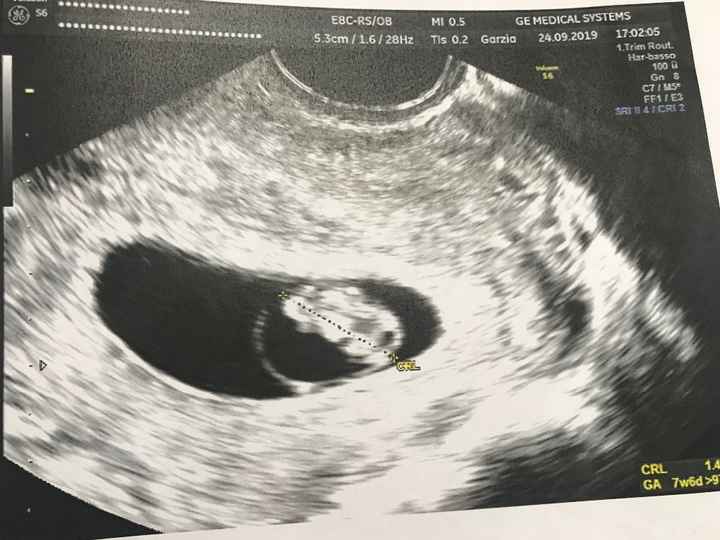

Altra domandina: l’11 ho fatto il dna fetale (con Nativa) e mi hanno detto che se entro 7 giorni non mi fanno sapere nulla di chiamare, ma secondo voi devo calcolare i sabati e le domeniche? Così il tempo si allunga e questi giorni sembrano non passare mai 😓😓 grazie a tutte quelle che capiranno la

mia ansia 😂😂